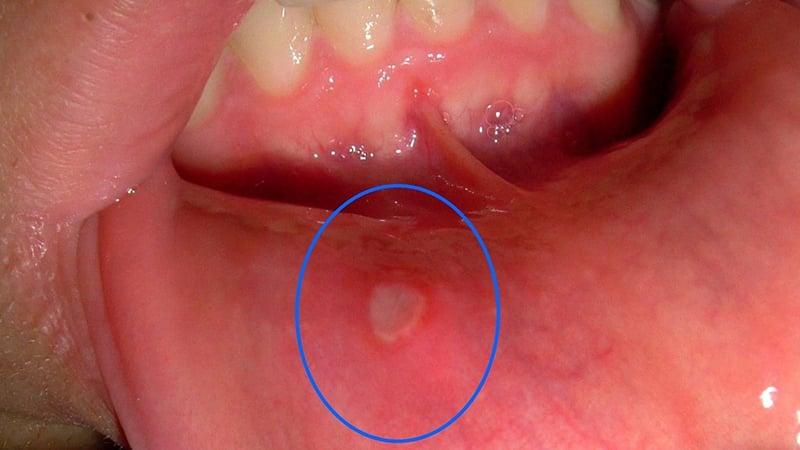

Очаг воспаления может вызывать жжение и болезненные ощущения. Часто пациенты сообщают о появлении белой болячки под языком. Лечение в этом случае следует начинать незамедлительно, так как наличие такой ранки в ротовой полости вызывает значительный дискомфорт, затрудняя прием пищи и разговор.

| Афтозный стоматит (рецидивирующий афтозный стоматит) | Наиболее частая причина язв под языком. Представляет собой небольшие, болезненные, круглые или овальные язвочки с красным ободком и белым или желтоватым центром. | Точная причина неизвестна, но связывают с генетической предрасположенностью, стрессом, травмами, дефицитом витаминов (B12, фолиевая кислота, железо), гормональными изменениями, некоторыми продуктами питания, ослабленным иммунитетом. |